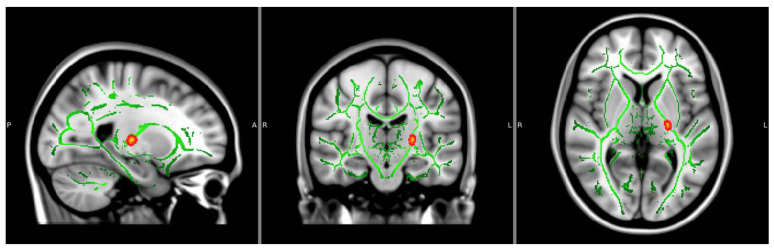

3.2. White Matter Integrity

Fractional Anisotropy: There was a main effect of NTP use groupings on FA values within the left posterior limb of the internal capsule (p < 0.05, TFCE corrected), showing decreased FA values within the NTP use group compared to NTP controls, controlling for age and biological sex (see Figure 1 and Table 2). FA findings continued to be significant after extracting estimates and controlling for past year alcohol use. There were no significant effects of cannabis use groups or the interaction between NTP and cannabis use groupings.

Table 2: Significant clusters.

| FA Values | Voxels | MAX | MAX X (vox) | MAX Y (vox) | MAX Z (vox) |

| 22 | 0.95 | −23 | −19 | 2 | |

| OD Values | Voxels | MAX | MAX X (vox) | MAX Y (vox) | MAX Z (vox) |

| 39 | 0.958 | −16 | −11 | −5 | |

| 27 | 0.962 | −16 | −5 | 5 | |

| 17 | 0.956 | −21 | −16 | 1 |

Notes: Voxels represent the number of voxels in each significant cluster. Max represents the maximum beta value within the cluster. MAX X/Y/Z is the location of the maximum intensity voxel. FA = fractional anisotropy. OD = orientation dispersion.